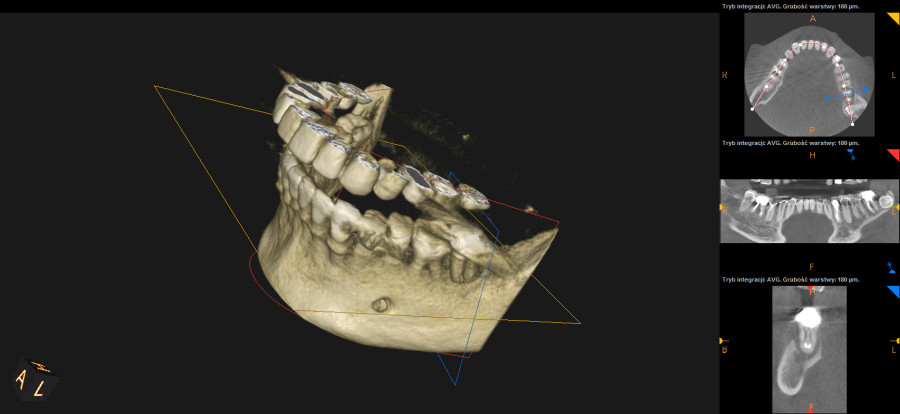

Ten problem najczęściej dotyczy zębów trzonowych żuchwy oraz górnych przedtrzonowców. Może również towarzyszyć wadom zgryzu, w zębach zniszczonych przez erozję, abrazję lub atrycję. Pionowe złamanie korzenia jest trudne do zdiagnozowania. Zdjęcia RTG nie zawsze bowiem ukaże „całą prawdę”. Coraz powszechniej używane obrazowanie CBCT (3D) pomaga w postawieniu diagnozy pionowego złamania zęba lub korzenia.

Nadzieją na przywrócenie funkcji żucia w zakresie utraconego zęba jest oczywiście – implant. Dynamiczny rozwój implantologii pozwala na uzupełnienie braków zębowych szybko, przewidywalnie i bezboleśnie.